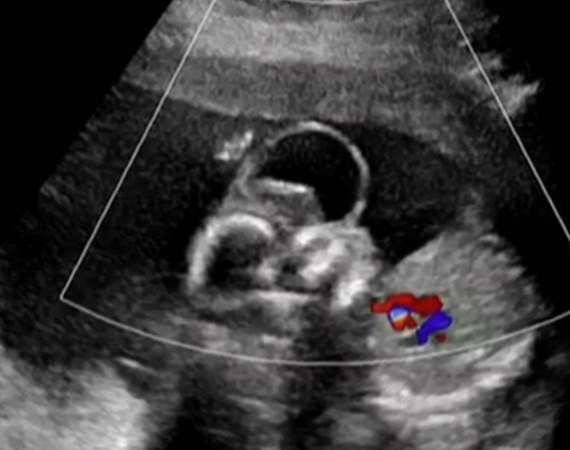

Thembe与Sipho是一对平凡的夫妻,他们盼望孩子的到来,所以Thembe怀孕后两人格外开心。怀孕21週时,Thembe去医院做检查,医生说的话却让她彻底心碎。

▼医生发现她腹中的孩子先天畸形,大脑长在头外面,甚至说他无法长大成人,建议终止妊娠。